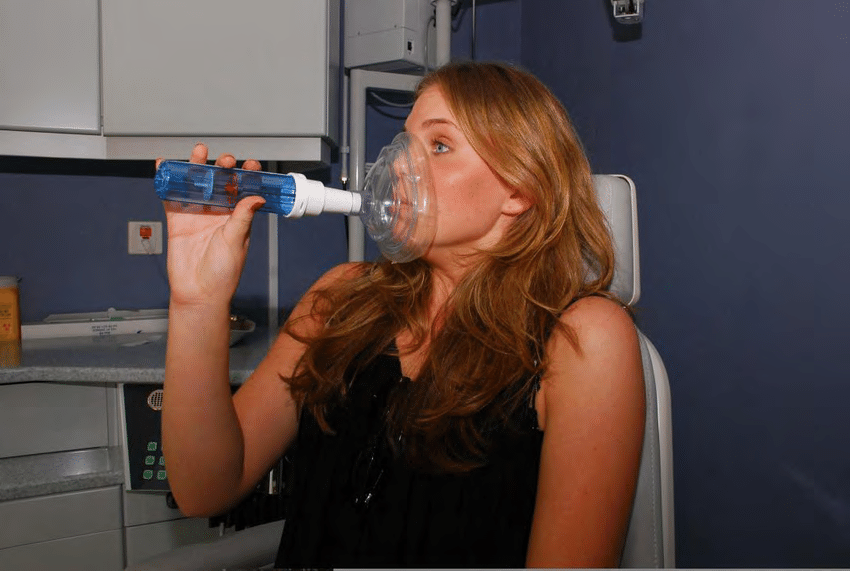

En la Clínica Mompell & Micó, sabemos que el primer paso para ofrecerte el mejor tratamiento es un diagnóstico completo y preciso. Con tecnología avanzada y un equipo especializado, aseguramos que cada detalle sea considerado para ofrecerte el mejor plan de tratamiento personalizado.